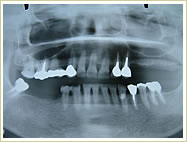

症例 63歳 女性 インプラント埋入数:2個 1本 画像拡大

治療前 治療後